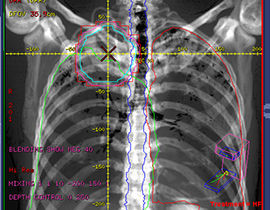

Advanced Visualization für die interventionelle Bildgebung